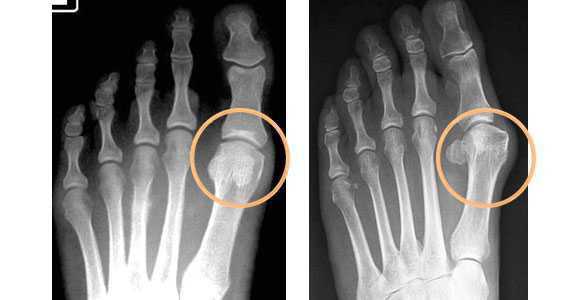

Диагноз поперечное плоскостопие выставляется на основании данных внешнего осмотра и результатов рентгенографии стопы. Для получения полной картины заболевания обычно назначают рентгенографию I, II и III плюснефаланговых суставов. В процессе описания снимков рентгенолог оценивает выраженность вальгусной деформации I пальца с учетом угла между I пальцем и II плюсневой костью и угла между I и II плюсневыми костями. Выделяют три степени деформации:

- 1 степень - угол между I пальцем и II плюсневой костью не превышает 25 градусов, угол между I и II плюсневыми костями не превышает 12 градусов.

- 2 степень - угол между I пальцем и II плюсневой костью не превышает 35 градусов, угол между I и II плюсневыми костями не превышает 18 градусов.

- 3 степень - угол между I пальцем и II плюсневой костью превышает 35 градусов, угол между I и II плюсневыми костями превышает 18 градусов.

Рентгенография стопы. Поперечное плоскостопие. Угол между 1-й и 2-й плюсневой костью 11,1 град. (1-й ст.).